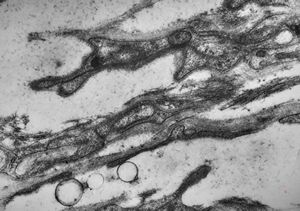

M,15y. | neurinoma - orbita